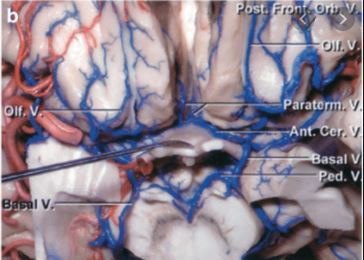

Which veins may drain an anterior fossa AVDF?

Retrograde venous drainage to cortical vessels (orbitofrontal and olfactory veins) which drain to the basal vein of Rosenthal and anterograde drainage to the superior sagittal sinus.